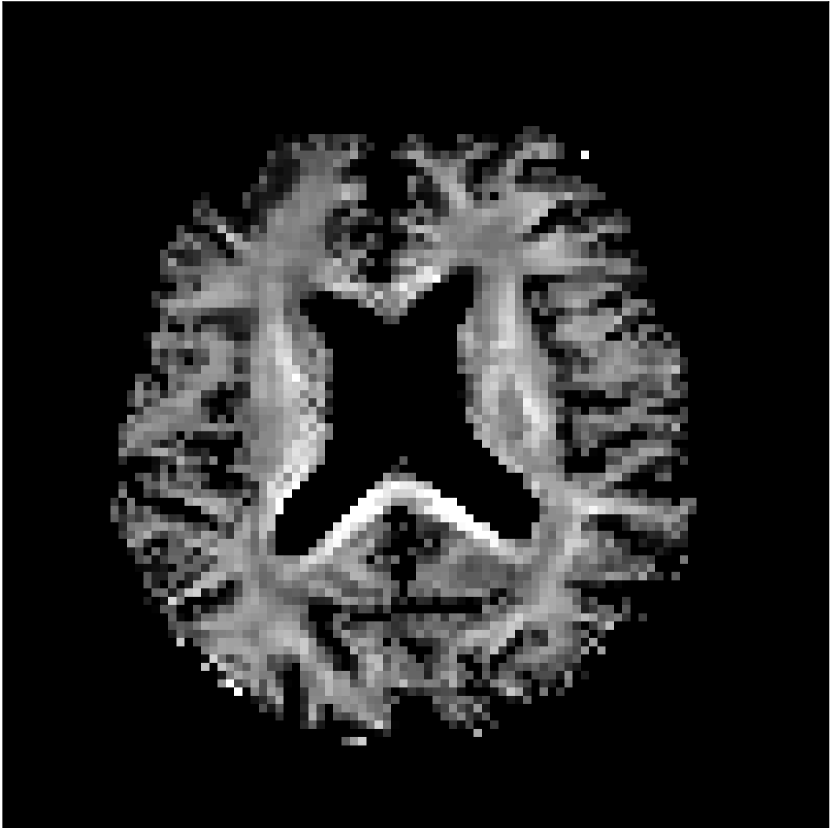

Figure 8 shows examples of non-diffusion-weighted images before and after processing. The raw images (Raw) served as the input for the magnitude deep learning (MCNN) and complex deep learning (CCNN) methods.

Raw 𝐱tsubscript𝐱𝑡\mathbf{x}_{t}

MCNN, fθ^(𝐱t)subscript𝑓^𝜃subscript𝐱𝑡f_{\hat{\theta}}\left(\mathbf{x}_{t}\right)

MCNN Resid., Ric(𝐱t)fθ^(𝐱t)Ricsubscript𝐱𝑡subscript𝑓^𝜃subscript𝐱𝑡\text{Ric}(\mathbf{x}_{t})-f_{\hat{\theta}}\left(\mathbf{x}_{t}\right)

CCNN, fθ^(𝐱t)subscript𝑓^𝜃subscript𝐱𝑡f_{\hat{\theta}}\left(\mathbf{x}_{t}\right)

CCNN Resid., Ric(𝐱t)fθ^(𝐱t)Ricsubscript𝐱𝑡subscript𝑓^𝜃subscript𝐱𝑡\text{Ric}(\mathbf{x}_{t})-f_{\hat{\theta}}\left(\mathbf{x}_{t}\right)

No PF

5/8 PF

Figure 8: Examples of non-diffusion-weighted images from in vivo data at b=0𝑏0b=0 s/mm2. Artifacts in the Raw image, 𝐱tsubscript𝐱𝑡\mathbf{x}_{t}, are corrected by the MCNN and CCNN models, fθ^(𝐱t)subscript𝑓^𝜃subscript𝐱𝑡f_{\hat{\theta}}(\mathbf{x}_{t}). Also shown are the residuals between the CNN corrections and the original Raw image with Rician bias correction Ric(𝐱t)Ricsubscript𝐱𝑡\text{Ric}(\mathbf{x}_{t}) [10]. The Gibbs artifacts removed by the methods are observed in the residuals. The MCNN method introduces some banding artifacts at the PF 5/8ths factor that are not present in the CCNN method.

Both methods remove artifacts, but the MCNN method allows residual rippling artifacts to pass through in the presence of partial Fourier. These rippling artifacts are not present in the CCNN method.